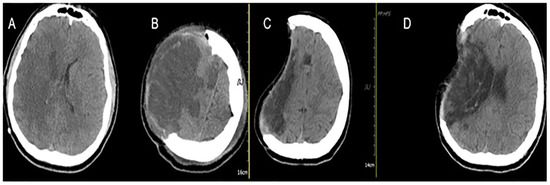

Illustrative Cases